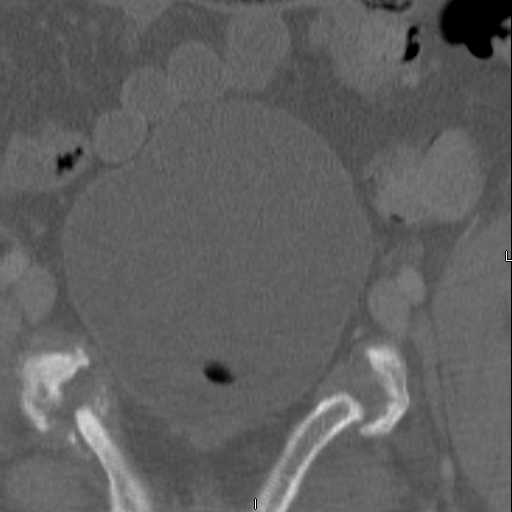

attached are images of a 59 yo female, admitted today after motor vehicle collision. Pt states her pelvis has been very painful ever since she fell on her buttocks from ground level a little over a year ago.

medical history significant for scleroderma, raynauds syndrome, and COPD. no past surgeries.

pt states she is very limited in walking ability secondary to pain. she requires a cane or a walker. friends and family do her shopping. the pain is localized primarily around left upper groin. she points to the rami region.

the question is if her medical history is contributing to the nonunions, and if anyone would consider surgical intervention, or is there some other successful intervention?